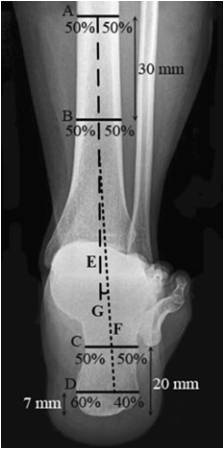

Saltzman

1.         确定胫骨长轴E

2.         确定跟骨长轴F

距跟骨最低处7mm处做水平线C,分为3:2

距跟骨最低处20mm处做水平线D:分为1:1

正常足:0°~5°

外翻足:5°~10°

严重外翻足:>10°

内翻足:0°~-10°

严重内翻足:<-10°